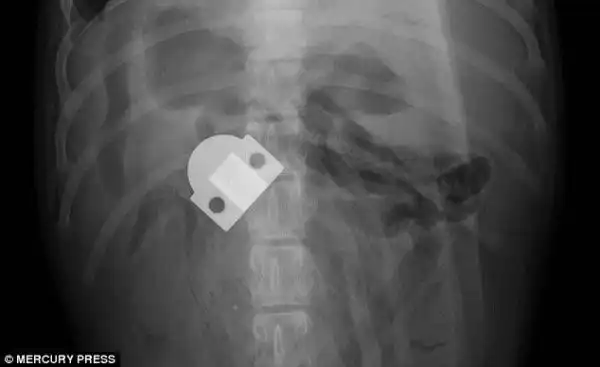

Врачи были очень удивлены, обнаружив большой кусок неизвестной массы в животе боксера

Как выяснилось, этой массой был огромный кусок клея, который по всей видимости собака стала есть в жидком состоянии, и который в последствии застыл у неё в животе